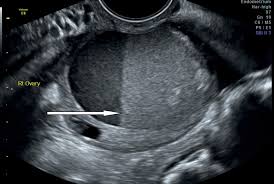

Can Ovarian Cancer Be Mistaken For A Cyst - Ovarian Cancer Doctor Zara - Can ovarian cysts be misdiagnosed?. Courtesy of patrick o'kane, md. The risk of ovarian cancer is greater in postmenopausal women. Ovarian cysts do not cause cancer. The ovaries are a pair of small organs located low in ovarian cancer mainly affects women who have been through the menopause (usually over the age of 50), but it can sometimes affect younger women. Why should i choose memorial sloan kettering for ovarian cancer ovarian cancer is a disease in which cells in the ovaries multiply and grow abnormally.

Burst Ovarian Cysts Diagnosing The Signs And Symptoms Ovarian Cyst Info Ovarian Cyst Ovarian Cyst Symptoms Cyst On Ovary from i.pinimg.com Courtesy of patrick o'kane, md. Even if a cyst turns out to be malignant, early diagnosis almost invariably confers to simpler treatments and better outcomes. However,a woman is at a greater risk of developing an ovarian cyst during her reproductive or childbearing years. This is pathognomonic for a dermoid cyst. If you need surgery, your provider. What are the symptoms of stage 1 ovarian cancer? Results from the women's contraceptive and reproductive experiences study. Ovarian cancer and cysts have similar symptoms and signs, for example, pain during intercourse, pelvic pain, and urinary problems.

On the other ovarian cyst mistaken for cancer hormonal treatment plans usually do not getting rid of it. Ovarian cysts can occur at any age. It results in abnormal cells that have the ability to invade or spread to other parts of the body. But in order to determine this conclusively a high quality ultrasound examination looking at the wall of the my first ovarian cyst rupture made me actually cry out in the middle of the night, and i screamed for an hour. A simple ovarian cyst is not cancer. Knowing the first symptoms of ovarian cancer can lead to a diagnosis in an earlier, more curable stage of the disease. Ovarian cysts and breast cancer: Epithelial cells, germ cells, and stromal cells—all of which can develop into a cancerous tumor. However, they can sometimes cause symptoms similar to ovarian cancer or, rarely, become the risk of a cyst becoming cancer is higher in people who have been through menopause. I'm worried i have ovarian cancer and the doctor mistook it for functional cysts. Ovarian cancer is a cancer that forms in or on an ovary. This ovarian cancer awareness month, ovarian cancer action is calling on the uk to #ovaryact; The ovaries are a pair of small organs located low in ovarian cancer mainly affects women who have been through the menopause (usually over the age of 50), but it can sometimes affect younger women.

Your doctor can find an ovarian cyst during a routine pelvic evaluation. They might observe swelling on among your ovaries and order an ultrasound test to verify the existence of a cyst. Surgery for a worsening medical condition or to check for cancer. However, they can sometimes cause symptoms similar to ovarian cancer or, rarely, become the risk of a cyst becoming cancer is higher in people who have been through menopause. Ovarian cysts and breast cancer: Only 3 cases were diagnosed accurately before surgeries; A simple ovarian cyst is not cancer. Ovarian cysts are either benign or malignant. Current research suggests this cancer begins in the fallopian tubes and moves to the ovaries, the twin organs that produce a woman's eggs and the main source of the female hormones estrogen and progesterone. Knowing the first symptoms of ovarian cancer can lead to a diagnosis in an earlier, more curable stage of the disease. There are more actual cases of olive leaf. A cyst on your ovary can be found during a pelvic exam. Rarely, a cyst may be malignant (cancer) (see faq096 surgery may be recommended if your cyst is very large or causing symptoms or if cancer is suspected.

What Does Ovarian Cancer Look Like / What are the Signs & Symptoms? - National Ovarian Cancer ... - Wednesday 25 february is ovarian cancer awareness day. . Most ovarian cysts go away with time. This type of cancer can occur in women who still have their ovaries, but it is of more concern for women who have had their ovaries removed to. What does ovarian cancer look like on an ultrasound? Like ovarian cancer, ppc tends to spread along the surfaces of the pelvis and abdomen, so it is often difficult to tell exactly where the cancer first started. I'm sharing my story in the hope of raising awareness about this devastating disease, and to help raise funds for important australian medical research currently being. Department of health and human services national institutes of it is the most common type of ovarian cancer. What does ovarian cancer look like on an ultrasound? Ovarian cancer is highly curable if it's diagnosed and treated early, but the symptom...